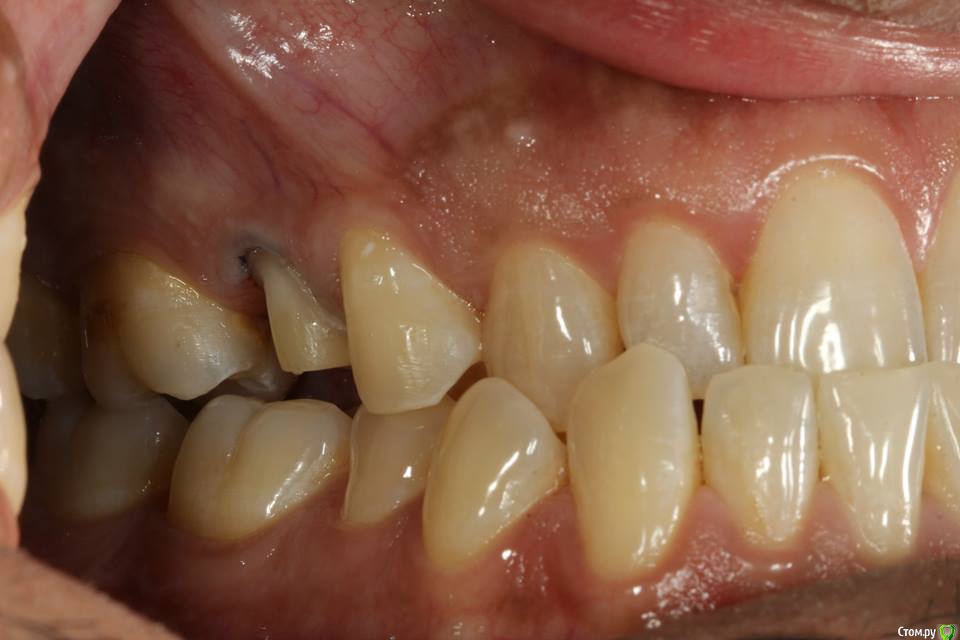

Kolchanov Опубликовано 23 июня, 2015 Поделиться Опубликовано 23 июня, 2015 Экструзия одиночного зуба для получения хоть какого-нибудь феррула. Подозреваю, что процедура не очень сложна и вполне модет быть освоена простым терапевтишкой, т.е. мной. Был бы очень благодарен, если бы кто-нибудь накидал своих мыслей по этому поводу, а еще лучше и фоток. И, конечно же, перечисление материалов. В одной из клиник, где я работаю, делают так иногда.После удаления штифтового зуба имеем поддесневой дефектhttp://s010.radikal.ru/i311/1506/49/4f3a03a5b53b.jpghttp://s010.radikal.ru/i313/1506/55/c752a532f478.jpgПациентка пожелала зуб сохранить. Теперь его тянут. И пятерочку еще в придачу.http://s014.radikal.ru/i327/1506/75/e9897bfb0e24.jpghttp://i024.radikal.ru/1506/99/1f1453b881ef.jpghttp://s017.radikal.ru/i434/1506/ea/caf4284659b4.jpghttp://s018.radikal.ru/i522/1506/ae/b2b54bddcdb8.jpghttp://s015.radikal.ru/i331/1506/7c/0efe752f8c35.jpgПока ничего сложного не вижу.У меня сейчас есть похожий случай. Но, послать в Москву... Не поедут. А на местного ортодонта как-то надежды мало. Я потом залью сюда фотки со своими мыслями. Может кто что присоветует...Спасибо! 1 Ссылка на комментарий

Romanson Опубликовано 25 июня, 2015 Поделиться Опубликовано 25 июня, 2015 Интересная тема, спасибо Колчанов за её создание. Вопрос такой - при ортоэкструзии обязательно нужно каждую неделю "подрезать" круговую связку? По теме есть вот такой кейс, автора к сожалению не помню. 2 Ссылка на комментарий